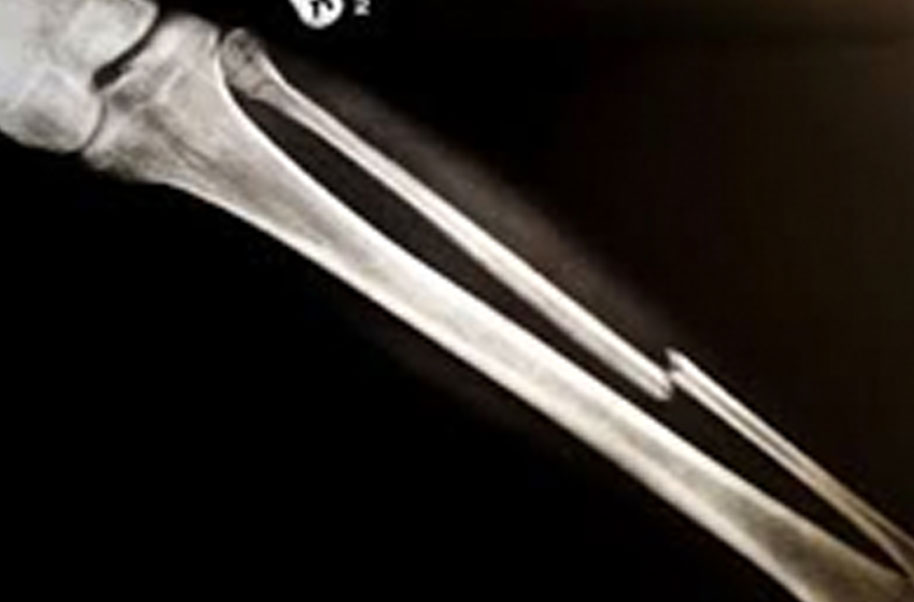

Ethmoid Bone (Broken Bone)

A complete or partial break in a bone.

- Treatment often involves resetting the bone in place and immobilising it in a cast or splint to give it time to heal. Sometimes, surgery with rods, plates and screws may be required.

Causes of bone fractures include trauma, overuse and diseases that weaken bones.